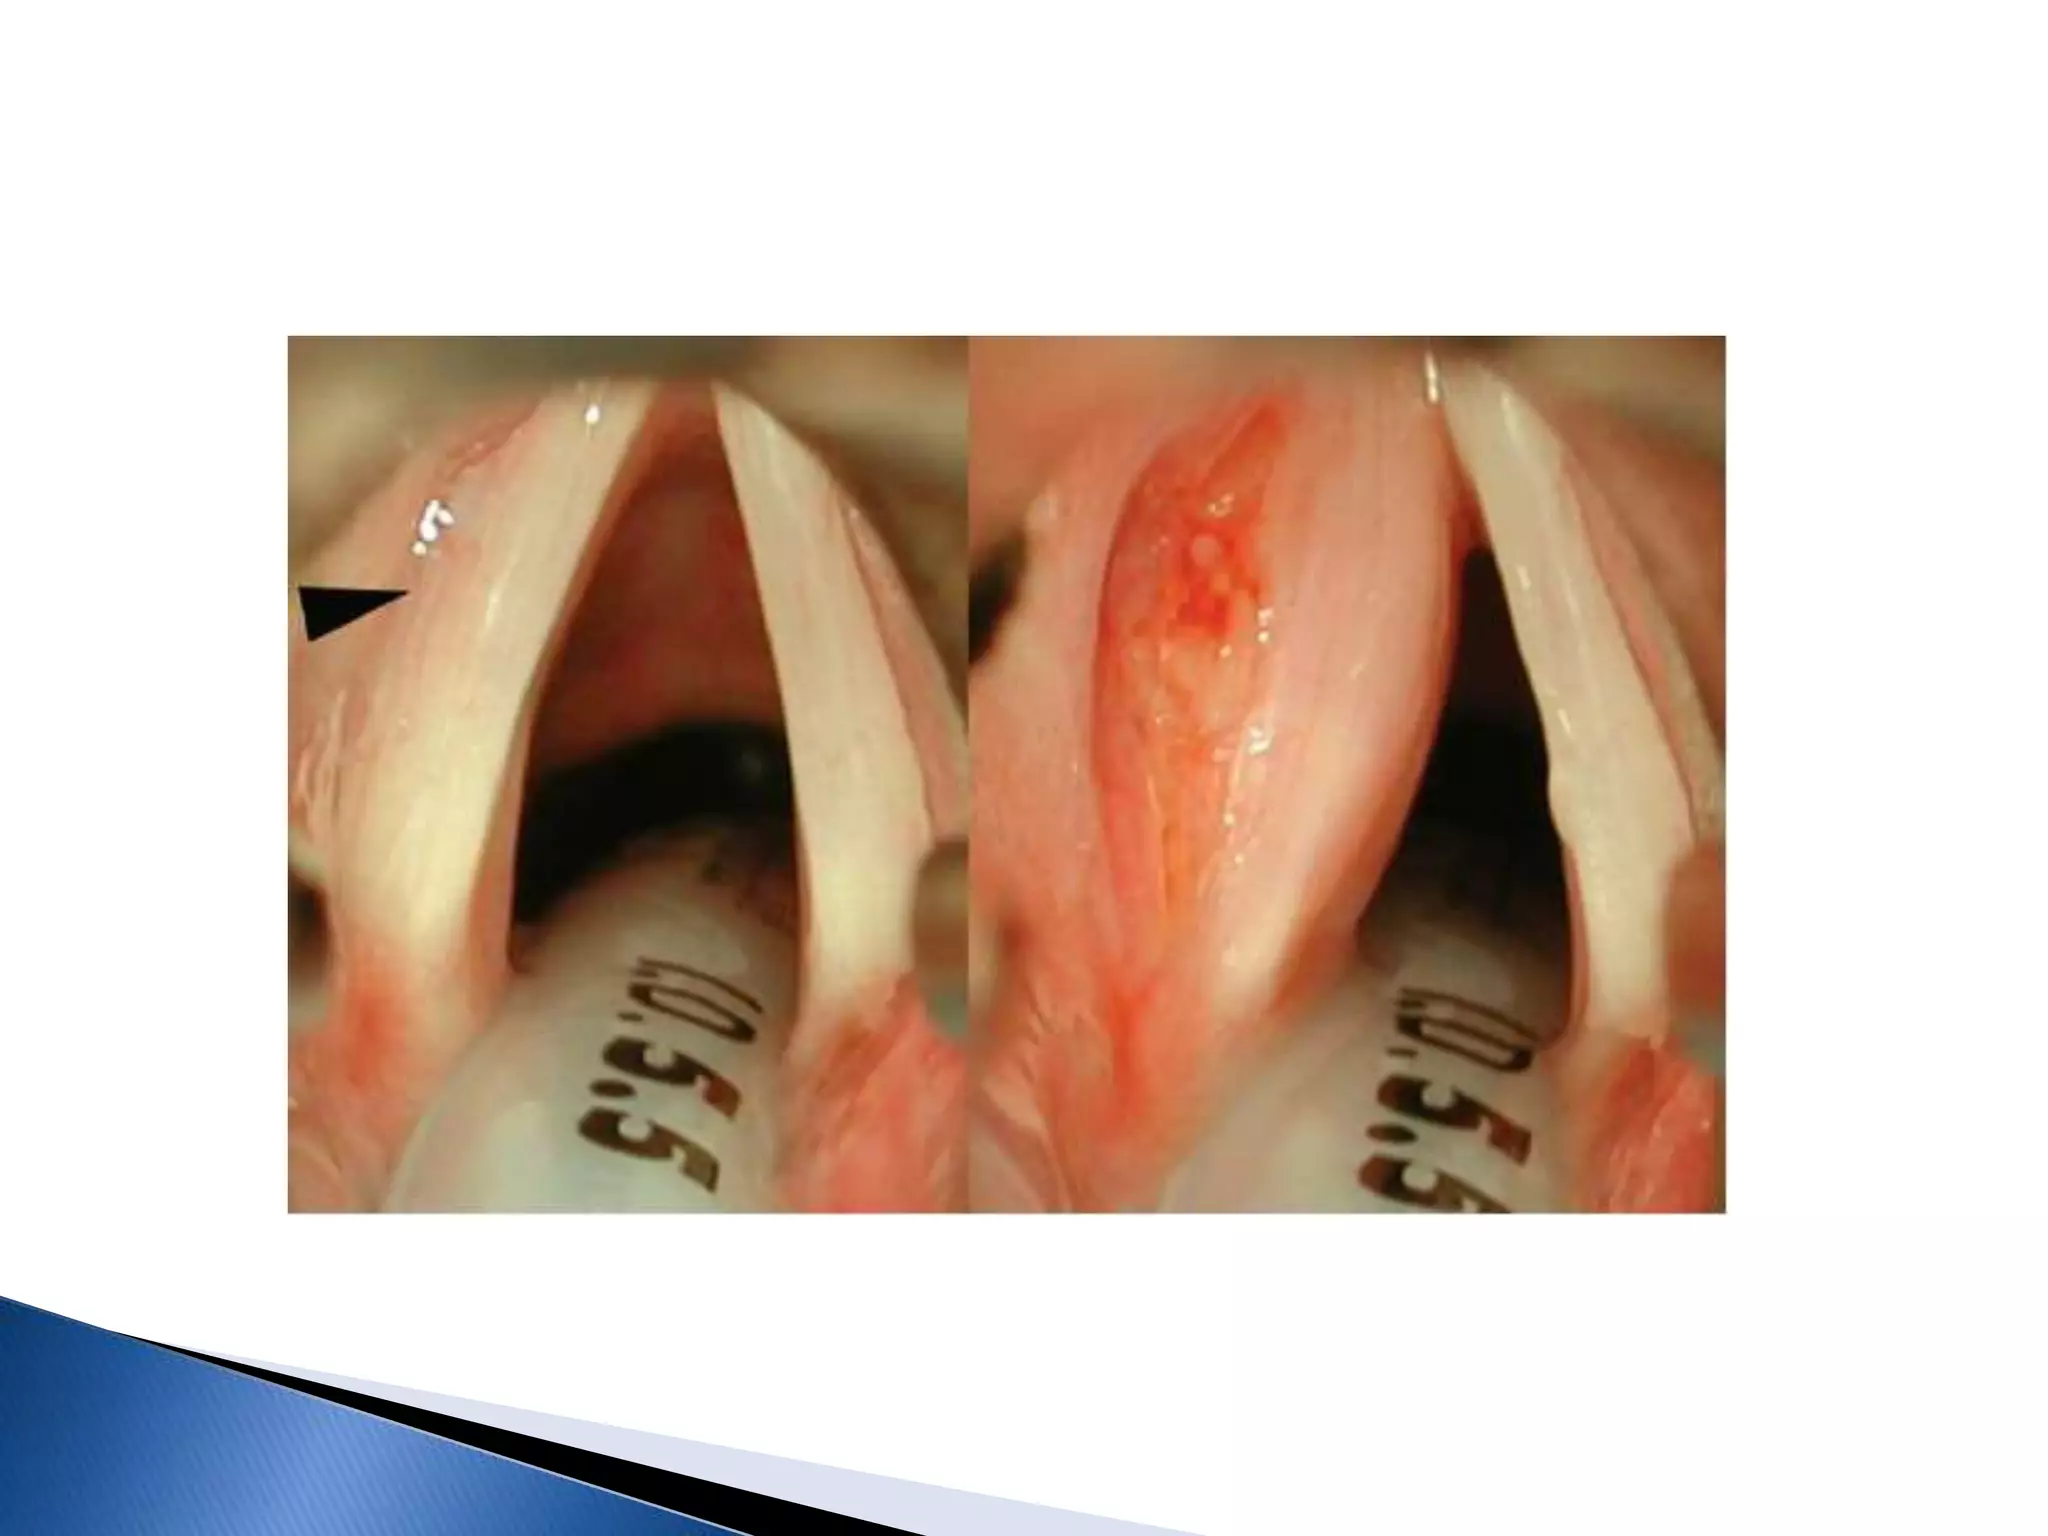

 Endoscopic CO2 LASER cordotomy ( Kashima Operation)

Soft tissue at the junction of membranous cord and vocal

process of arytenoid is excised laterally with laser, which

provides good airway.

 Medial part of arytenoid is excised with laser.

Sometimes only the vocal process of arytenoid

is ablated